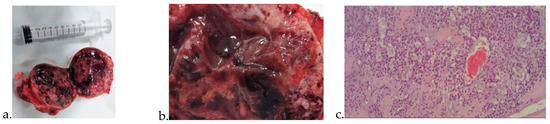

Glomangioma Supply from Profunda Femoris Artery in Peripheral Artery Disease

3. Results